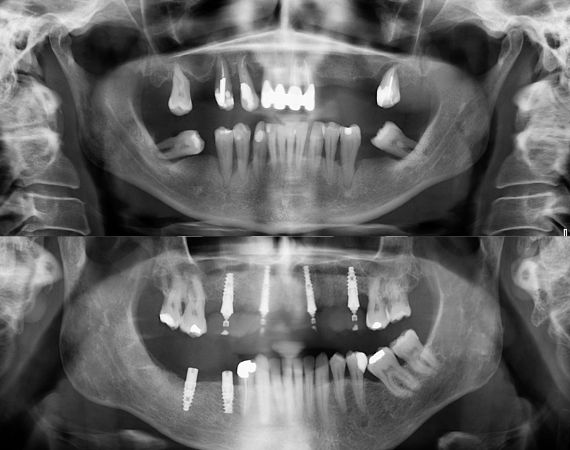

Antes y después implante